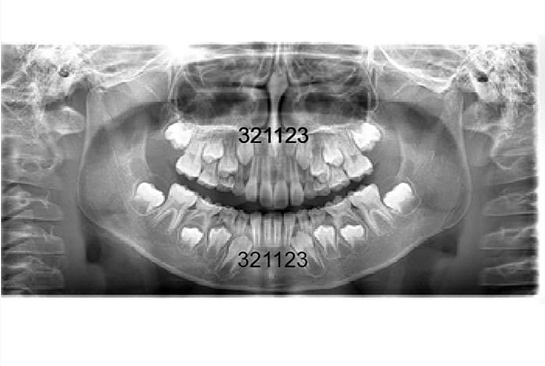

術前と術中のレントゲン写真

• 術前のレントゲン写真

上顎の3番目の犬歯のスペースがほとんどありません。 下顎も同じように3番目の犬歯のスペースが僅かですが不足しているのが解ります。 このままですと特に上顎の前歯は凸凹になり、犬歯は間違いなく八重歯になるでしょう。

• 術中のレントゲン写真

上顎の左右の2番目から2番目の4歯は綺麗にはえることができ、3番目の犬歯のスペースができました。 下顎も同じように3番目の犬歯のスペースができました。これで八重歯になる事はなく自然に萌出することを待ちます。